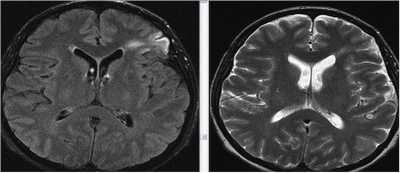

- магнітно-резонансна перевірка. Томографія може показати не тільки осередок гліоза в білій речовині головного мозку, але і можливі обставини, які спровокували дане явище.

- На знімках КТ (комп’ютерної томографії) можна простежити відхилення, які викликані збоєм функціонування судин або наявністю пухлин. Сканувати зміна в ділянці лобних часток дозволяє тільки цей метод дослідження. При множині варіанті гліоза технологія дозволяє знайти всі вогнища.